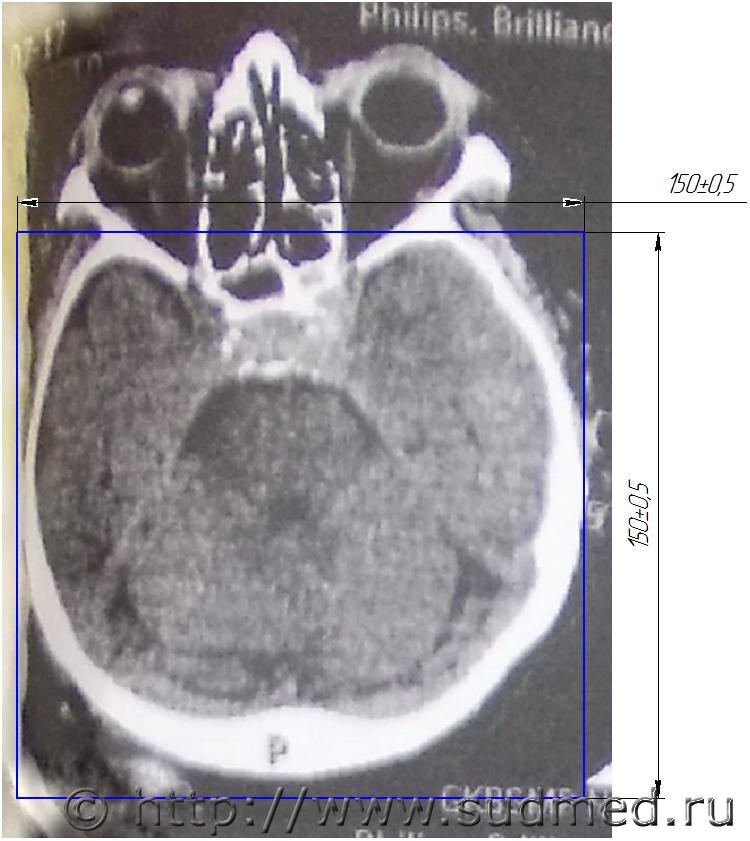

Моя цель, через имеющиеся зафиксированные повреждения доказать, что потерпевший их получил, при падении с высоты своего роста, и оспорить его утверждения что его многократно били по голове деревянной палкой. Это первый срез на уровне глаз

Эскизы прикрепленных изображений

Судебная медицина - Прикрепленное изображение

К сожалению, я не силен читать КТ. Если есть возможность, хотя бы приблизительно с учетом снимков КТ и рисунка черепа кто нибудь укажите место на рисунке приложения травмирующий силы с левой стороны. Оперирующий врач отказался от встречи.

В проекции левой теменной кости.